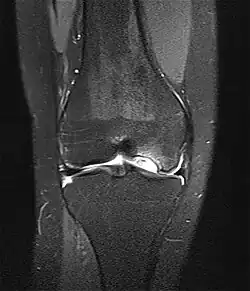

Die Erkrankung kann zufällig auf einem Röntgenbild entdeckt werden, das nach einem Unfall von der Knieregion, vom Sprunggelenk oder vom Ellbogen angefertigt wird. Bei typischen Beschwerden von aktiven Kindern und Jugendlichen kann mit einem solchen einfachen Röntgenbild die eindeutige Diagnose schon gestellt werden, weil der veränderte Knochen unterhalb der Gelenkoberfläche an typischer Stelle in der Oberschenkelrolle am Knie identifiziert werden kann. Manchmal kann eine sogenannte Tunnelaufnahme mit gebeugtem Knie die Schädigungszone noch besser zeigen. Zur genaueren Analyse sollte eine Kernspintomographie (MRT) durchgeführt werden. An den dabei erzeugten Bildern lässt sich die Lage und Größe des Befundes, die Tiefenausdehnung und vor allem eine Beteiligung des darüberliegenden Knorpels genau ausmessen. Es sind damit auch Aussagen zur Stabilität des Befundes zu treffen. Daraus ergeben sich dann entscheidende Anhaltspunkte für therapeutische Konsequenzen. Für die Verlaufsbeurteilung der Erkrankung eignet sich am besten das MRT, aber ggf. auch wieder die einfache Röntgenuntersuchung. Aufgrund der extrem hohen Kosten für das MR in den USA werden die Verläufe dort bis heute weitgehend nur mit Röntgenbildern dokumentiert, was zu eigenen Empfehlungen zur Verlaufsbeurteilungen führt. Generell wären aber die MR-Untersuchungen das Verfahren der Wahl. Sie erlauben eine differenzierte Beurteilung der unterschiedlichen Kriterien für Ausheilung, Instabilität und drohende Dissektion. Untersuchungen mit Sonographie können zuverlässige, aber nur orientierende Befunde am Femurkondylus erheben. Es ist damit zum Beispiel ein schneller, kostengünstiger und sicherer Ausschluss des Befalls auch der Gegenseite möglich.

Die Therapie der Osteochondrosis dissecans am Kniegelenk ist zunächst abhängig von der relativen Größe der Läsion im Vergleich zur Kondyle. Es gibt OCD an der medialen und an der lateralen Oberschenkelrolle (Kondyle). Selten kommt die Veränderung auch am Gleitlager gegenüber der Kniescheibe und an der Kniescheibe selber vor. Ein weiteres wichtiges Entscheidungskriterium ist das Stadium (stabil / instabil) der Läsion. Als Instabilitätszeichen tritt im MRT eine Zystenbildung, eine Vorwölbung des Knorpel-Knochen-Dissekates, ein Bruch der subchondralen Knochenlamelle und eine Rissbildung im Knorpel deutlich hervor. Ein wichtiges klinisches Symptom einer Instabilität des OD-Herdes ist eine Blockierung in der Gelenkfunktion, die als Zeichen der Beteiligung der Gelenkfläche an dem Erkrankungsprozess auftreten. Zusätzlich spielt das Alter des Patienten eine gewisse Rolle. Bei noch weit offenen Wachstumsfugen – also bei Jungen bis zum 14. und bei Mädchen bis zum 13. Lebensjahr – sind die spontanen Heilungsaussichten besser. Im Durchschnitt heilen bei allen Studien ca. 50 % der OCD-Fälle am Kniegelenk ohne operative Maßnahmen aus. Die komplette Ausheilung erfordert immer Monate bis Jahre, weil der notwendige Knochenumbau (Remodeling) durch Osteoklasten und Osteoblasten lange Zeit in Anspruch nimmt. Hierzu müssen ja knöcherne Strukturen aufgelöst, abtransportiert und wieder aufgebaut werden. Die therapeutischen Maßnahmen können aber je nach Fortgang der Heilung schon vor dessen komplettem Abschluss beendet werden.